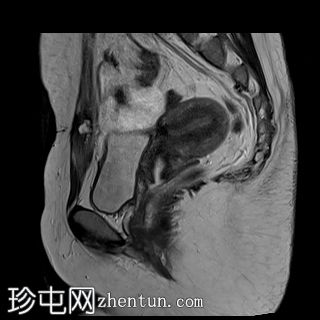

矢状位

T2加权像

MRI特征符合剖宫产术后瘢痕子宫内膜异位症,表现为特征性T1高信号伴T1FS持续存在,T2低信号伴内部高信号灶,病灶边缘浸润于腹前壁肌肉内,以及对比增强。

影像学表现符合病灶内出血成分,提示既往剖宫产瘢痕处存在异位子宫内膜组织。

子宫可见剖宫产瘢痕灶。